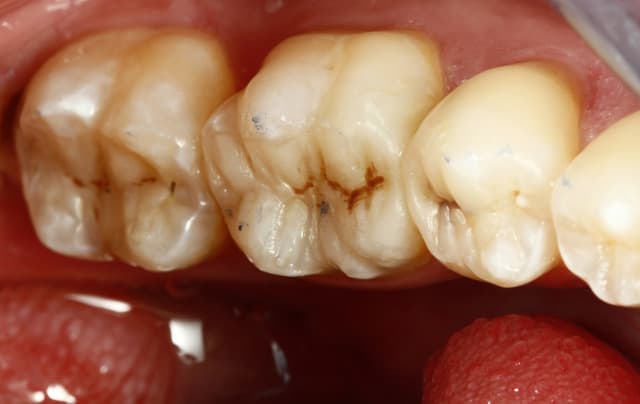

un truc que je fais souvent, quand je monte deux compo volumineux en contact, je monte le plus gros et difficile sans matrice et comme ça j'ai accès a la marge, et je peux donner une jolie forme galbée proximale

puis je monte le suivant avec une seule matrice...

plus facile je trouve d'avoir le point de contact